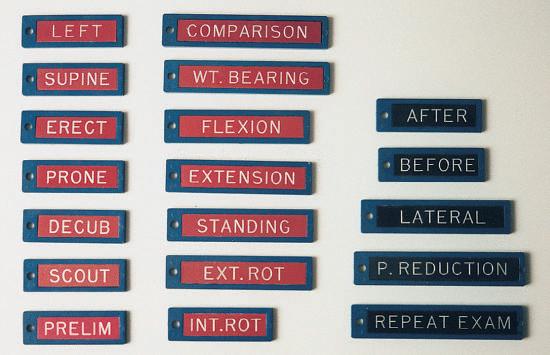

Positioning Principles Evaluation criteria, 30 Image markers and patient identification, 31 Professional ethics and patient care, 32 Essential projections, 33 Principles of positioning, 33 Palpation of positioning landmarks, 35 Viewing images, 35